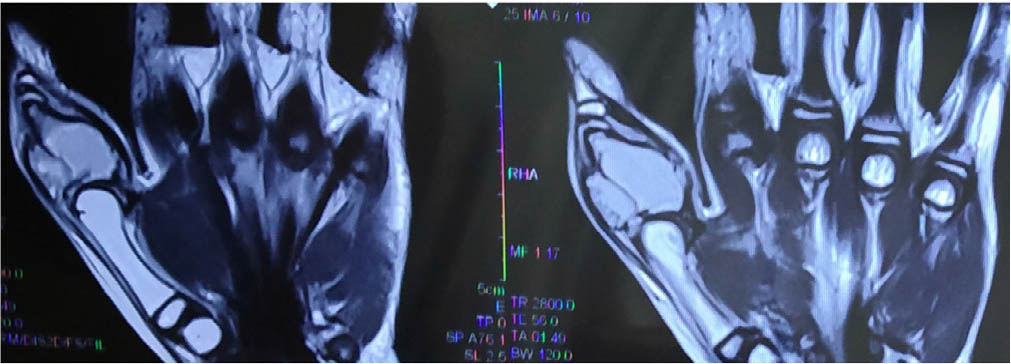

On examination there was swelling and mild tenderness of both thumbs; the overlying skin appeared normal (Figure 1). There was no history of trauma. Differential diagnosis included connective tissue disorder, abscess caused by tuberculosis, fracture and true tumour. The child had no history of fever or any skin rash, and radiological findings were not suggestive of any infective or inflammatory pathology. Involvement of the thumb in disseminated tuberculosis without the involvement of any other system was unlikely. Fracture was unlikely due to the lack of trauma, and tumours involving bilateral thumbs is extremely rare. Straight X-ray of the hand showed a lytic bone lesion with prominent internal trabeculation in the bilateral proximal phalanx of the thumb. Magnetic resonance imaging (MRI) showed an expansile altered signal intensity in the proximal phalanx of thumb on both sides (left>right) with outward bulging of subcutaneous fat all around with maintained adjoining joint spaces suggestive of pseudotumour (Figure 2).

Figure 2

Magnetic resonance imaging of right thumb (hyperintense lesion of proximal phalanx with liquefacation)